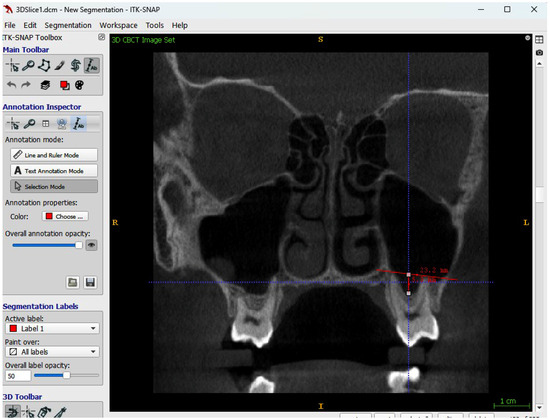

Comparison of Two Methods for Assessing the Maxillary Sinus Volume in Patients with and Without Unilateral Cleft Lip and Palate: A Retrospective Cross-Sectional Study

Background/Objectives: The aim of this study was to compare two methods for maxillary sinus volume measurement, assessing their accuracy. The analysis compared the maxillary sinus volume in patients with unilateral cleft lip and palate (UCLP) and in a non-cleft group, using a manual method and a three-dimensional (3D) semi-automated segmentation method. Methods: The research was conducted according to the STROBE guidelines. Sixty patients were included in this study: thirty patients with UCLP were in the research group, and the control group consisted of 30 patients with no craniofacial deformities. Cone-beam computed tomography (CBCT) was analyzed. The manual maxillary sinus volume was calculated based on its approximation to two geometric shapes based on mathematical formulas using linear measurements that were performed on all sinus CBCT scans in the maximum diameter in three planes. The semi-automatic segmentation method using ITK-SNAP 3D-imaging software version 4.2.2 was used to automatically calculate the maxillary sinus volume of the sinuses. The manually calculated volume was compared with the automatically calculated one, and statistical analysis was performed. Results: The cleft group presented lower values in both the automatic and manually calculated volumes for both the right (automatic: p = 0.49; manual p = 0.009) and left (automatic: p = 0.46; manual p = 0.11) maxillary sinuses than the non-cleft group. The cleft group presented statistically significant higher discrepancies in values between the manual and semi-automatic method than the control group (RMSV p = 0.0011; LMSV p = 0.033; TMSV p = 0.003). Conclusions: The manual method may not reveal the exact anatomical topography of the maxillary sinuses. In UCLP patients, the maxillary sinus anatomy may be more complex. Therefore, a semi-automated method may be more advisable to preserve the accuracy of the measurements. Full article

Show Figures

Figure 1